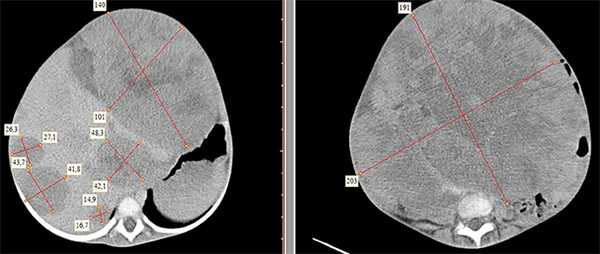

- Компьютерная томография органов брюшной полости и забрюшинного пространства с оральным и внутривенным контрастированием (см. рис. 1).

- Диагностика метастазов включает рентгенографию грудной клетки; при подозрении на метастазы в легкие — КТ органов грудной клетки. УЗИ брюшной полости и забрюшинного пространства также оценивает метастазы в регионарные лимфоузлы, печень, другие органы и ткани, выпот в брюшную полость.

Рисунок 1. КТ брюшной полости ребенка с большой нефробластомой с метастазами в печень.

Клинически: при пальпации опухоль в проекции правой почки до 12 см в диаметре. Общеклинические исследования в пределах возрастной нормы. При КТ органов брюшной и грудной полости: КТ-картина объемного образования правой почки без признаков интрапульмональных метастазов (см. рис. 2). УЗИ брюшной полости: в проекции правой почки солидно-кистозное образование 101ґ114ґ99 мм, объемом 500 мл, васкуляризация активная, интактная часть почки 57ґ12ґ40 мм. Объемное образование правой почки — опухоль Вильмса. Предварительный диагноз: опухоль Вильмса правой почки, 2-я стадия.

Ребенку проведена предоперационная химиотерапия. На 5-й неделе лечения КТ-контроль показал уменьшение опухоли в размерах до 90ґ80ґ100 мм (см. рис. 3).